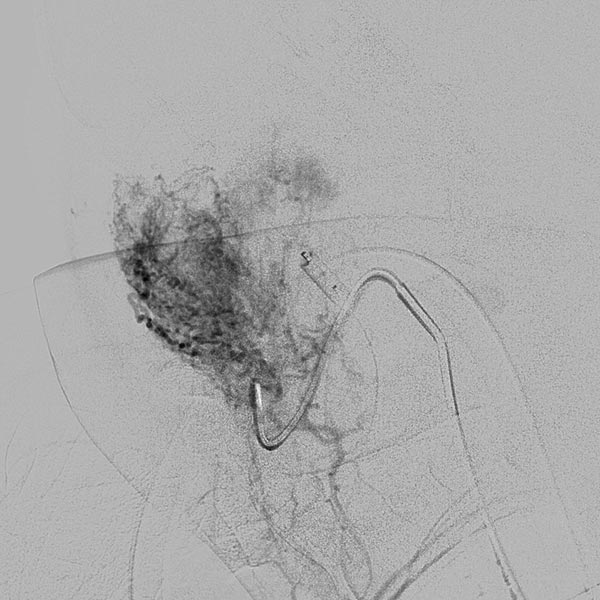

Digital subtraction angiography (DSA) after further super-selective injections with particles via a microcatheter while blocking the venous outflow. A good 50% of the infantile hemangioma has now been successfully occluded.

Digital subtraction angiography (DSA) after super-selective catheterization of the remaining arterial feeder supplying the infantile hemangioma.

During super-selective particle embolization (150 micron particles) via the arterial microcatheter after blocking out the venous outflow, the particles can be seen as a faintly contrasted area.

In the transarterial control angiography via the 4F diagnostic catheter, the infantile hemangioma is not perfused anymore. The typical DSA image of a “defoliated tree” is now shown.

Overview angiography via the common carotid artery after removal of the venous blocking balloon displays a virtually completely devascularized infantile hemangioma. The intracerebral circulation is normal.